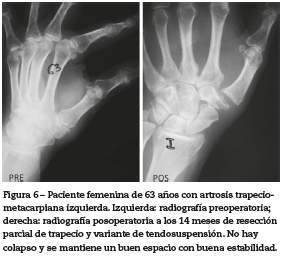

En el grupo 2: todas mujeres, edad promedio de 61 años (52-71), estado radiológico en 18 manos estadio 3 y 3 con estadio 2, el dolor preoperatorio era de 8,35 (7-9) en promedio y al final de 0,95 (0-2) (tabla 2).

La movilidad en abducción fue de 33° y el arco de flexión de 36,4°. Todas estaban satisfechas con la cirugía (fig.6).